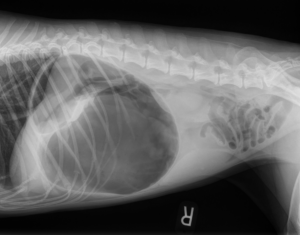

Surgery, Urgent Care and Emergency Services

A prophylactic gastropexy is a preventive surgical procedure that tacks the stomach to the abdominal wall to stop it from twisting. This twist, known as Gastric Dilatation Volvulus...